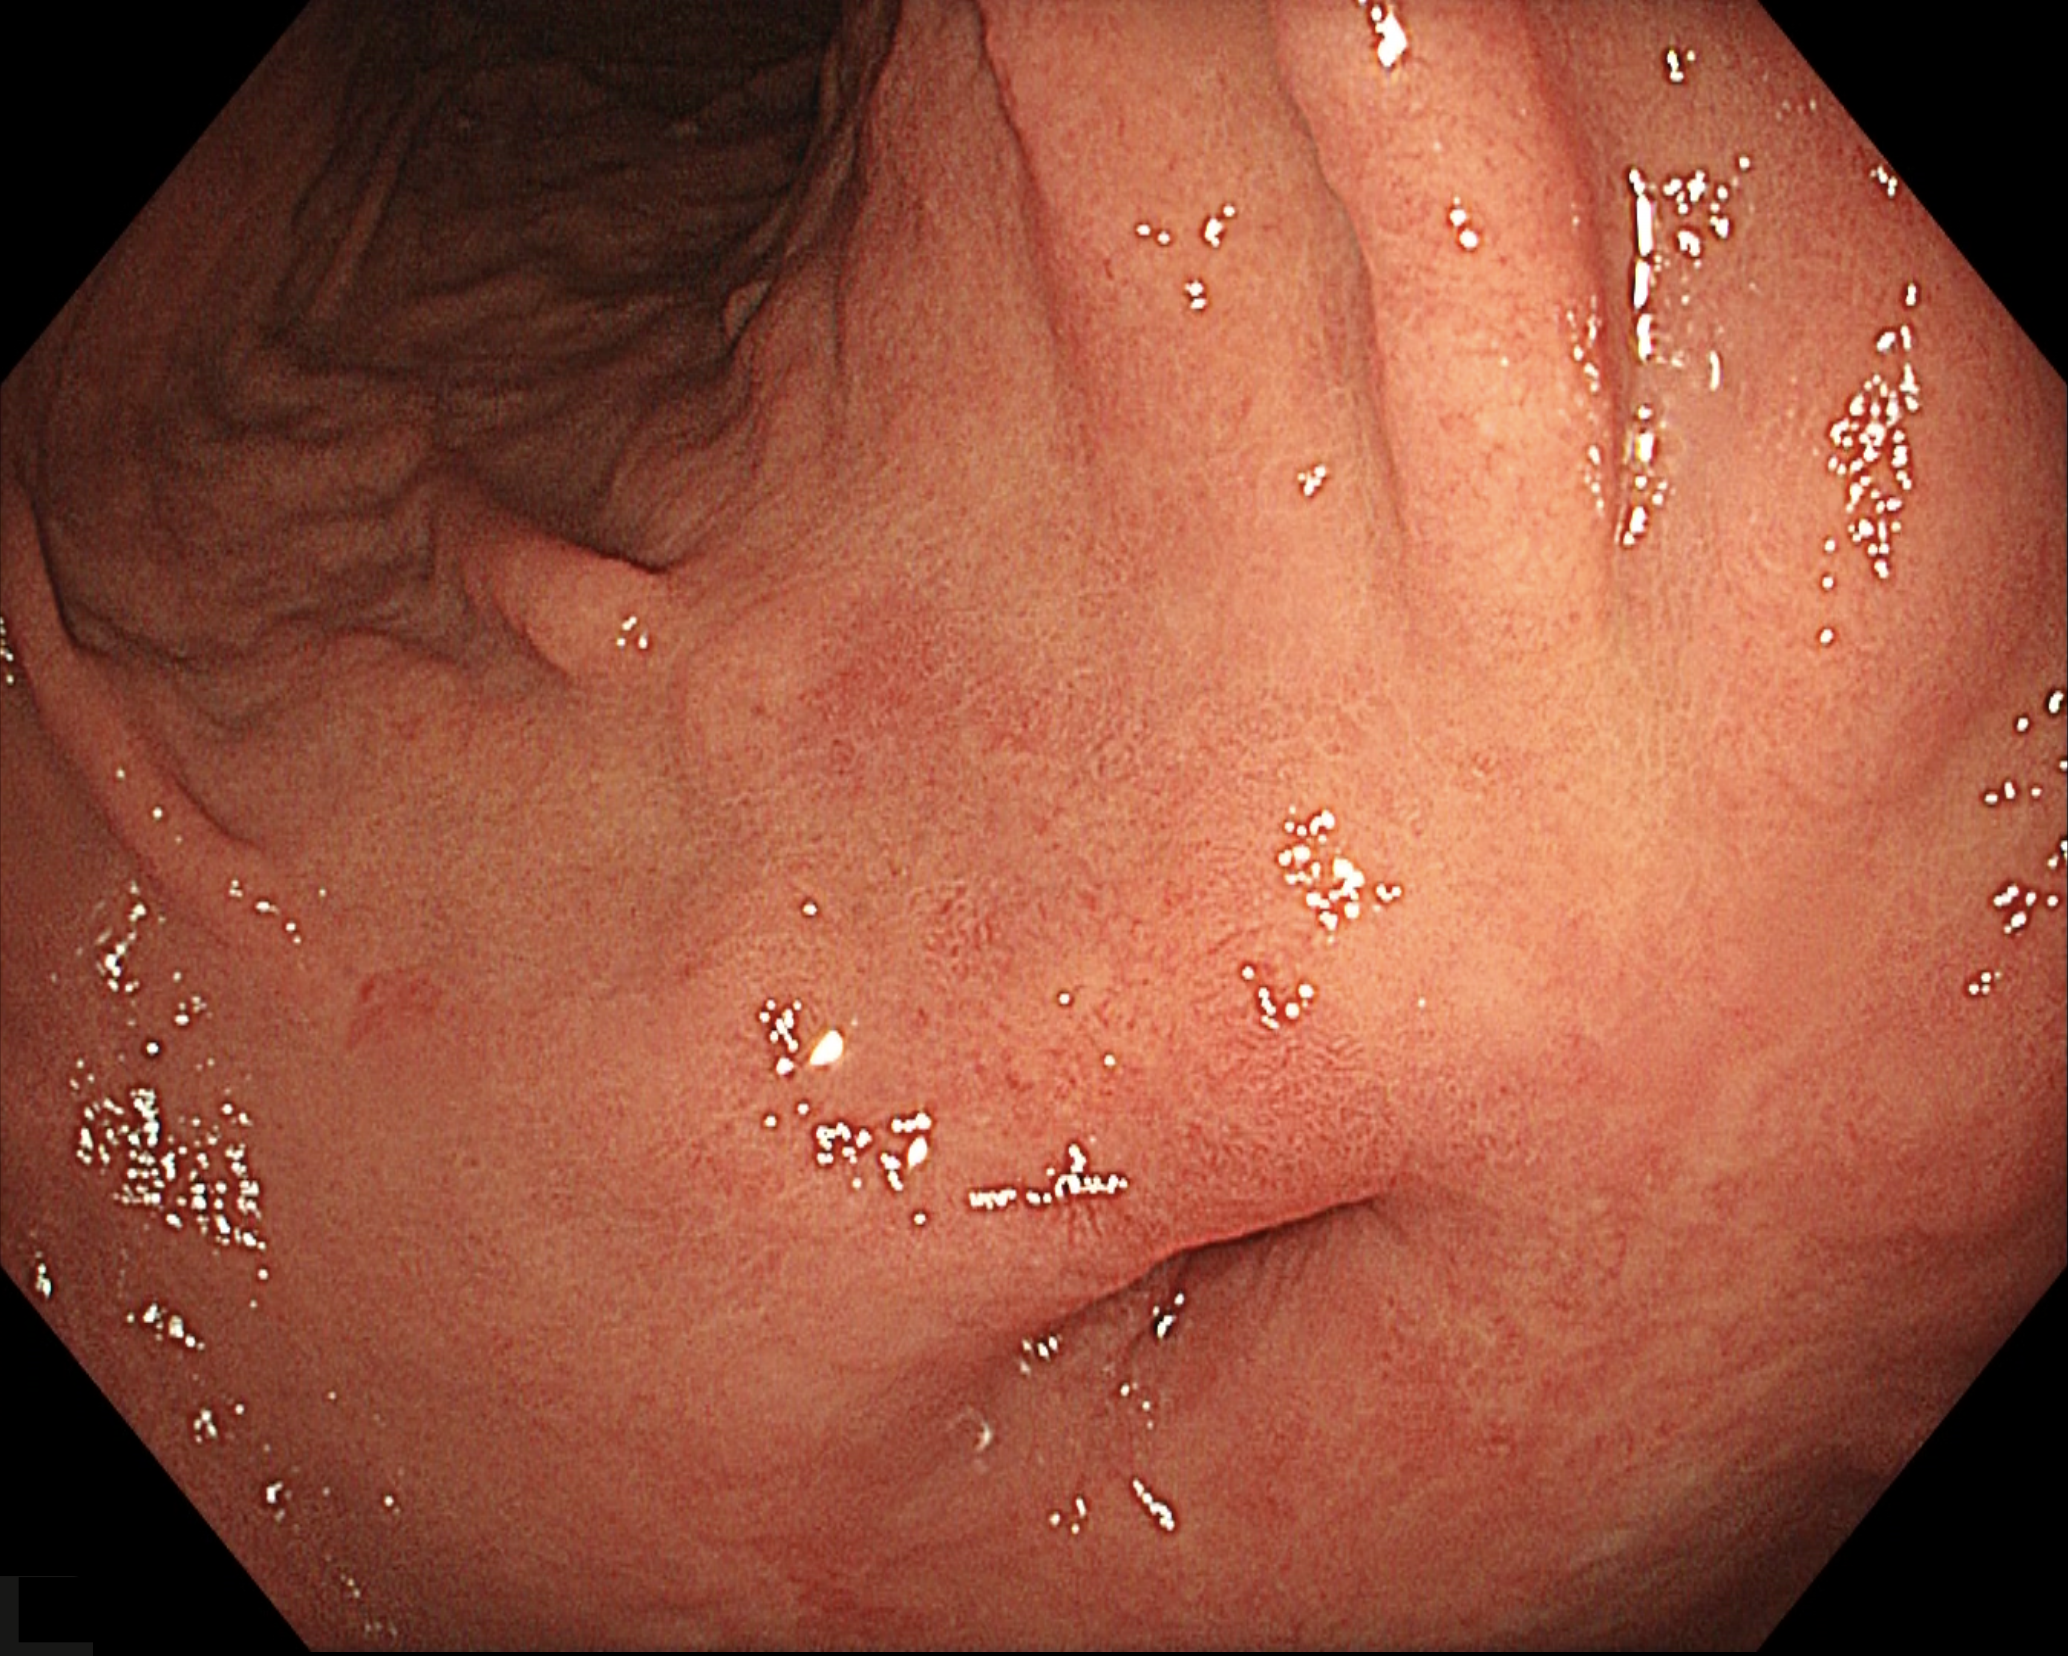

• 白色光観察(中遠景)

強調設定:A8

図1

胃前庭部後壁に悪性リンパ腫治療後の瘢痕および襞集中像、幽門輪の変形を認める。病変部は前庭部小彎に位置し、15mm大の発赤調陥凹性病変である。